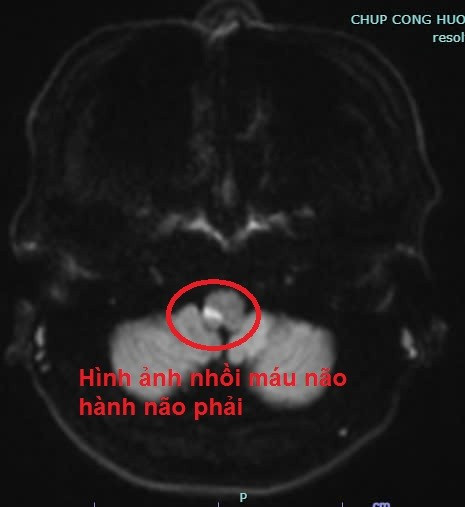

Ngay khi vào Trung tâm Đột quỵ, người bệnh được thăm khám và chẩn đoán ban đầu là có tình trạng rung giật nhãn cầu, nhìn đôi, tê yếu 1/2 người phải, cơ lực 3-4/5. Người bệnh được chỉ định chụp cộng hưởng từ sọ não, kết quả cho thấy có hình ảnh nhồi máu não hành não phải. Nguyên nhân gây ra tình trạng trên là do tắc một nhánh mạch nhỏ của hệ tuần hoàn não. Người bệnh được chẩn đoán đột quỵ nhồi máu não cấp hành não phải.

| Hình ảnh chụp cộng hưởng từ cho thấy người bệnh bị nhồi máu não hành não phải. |